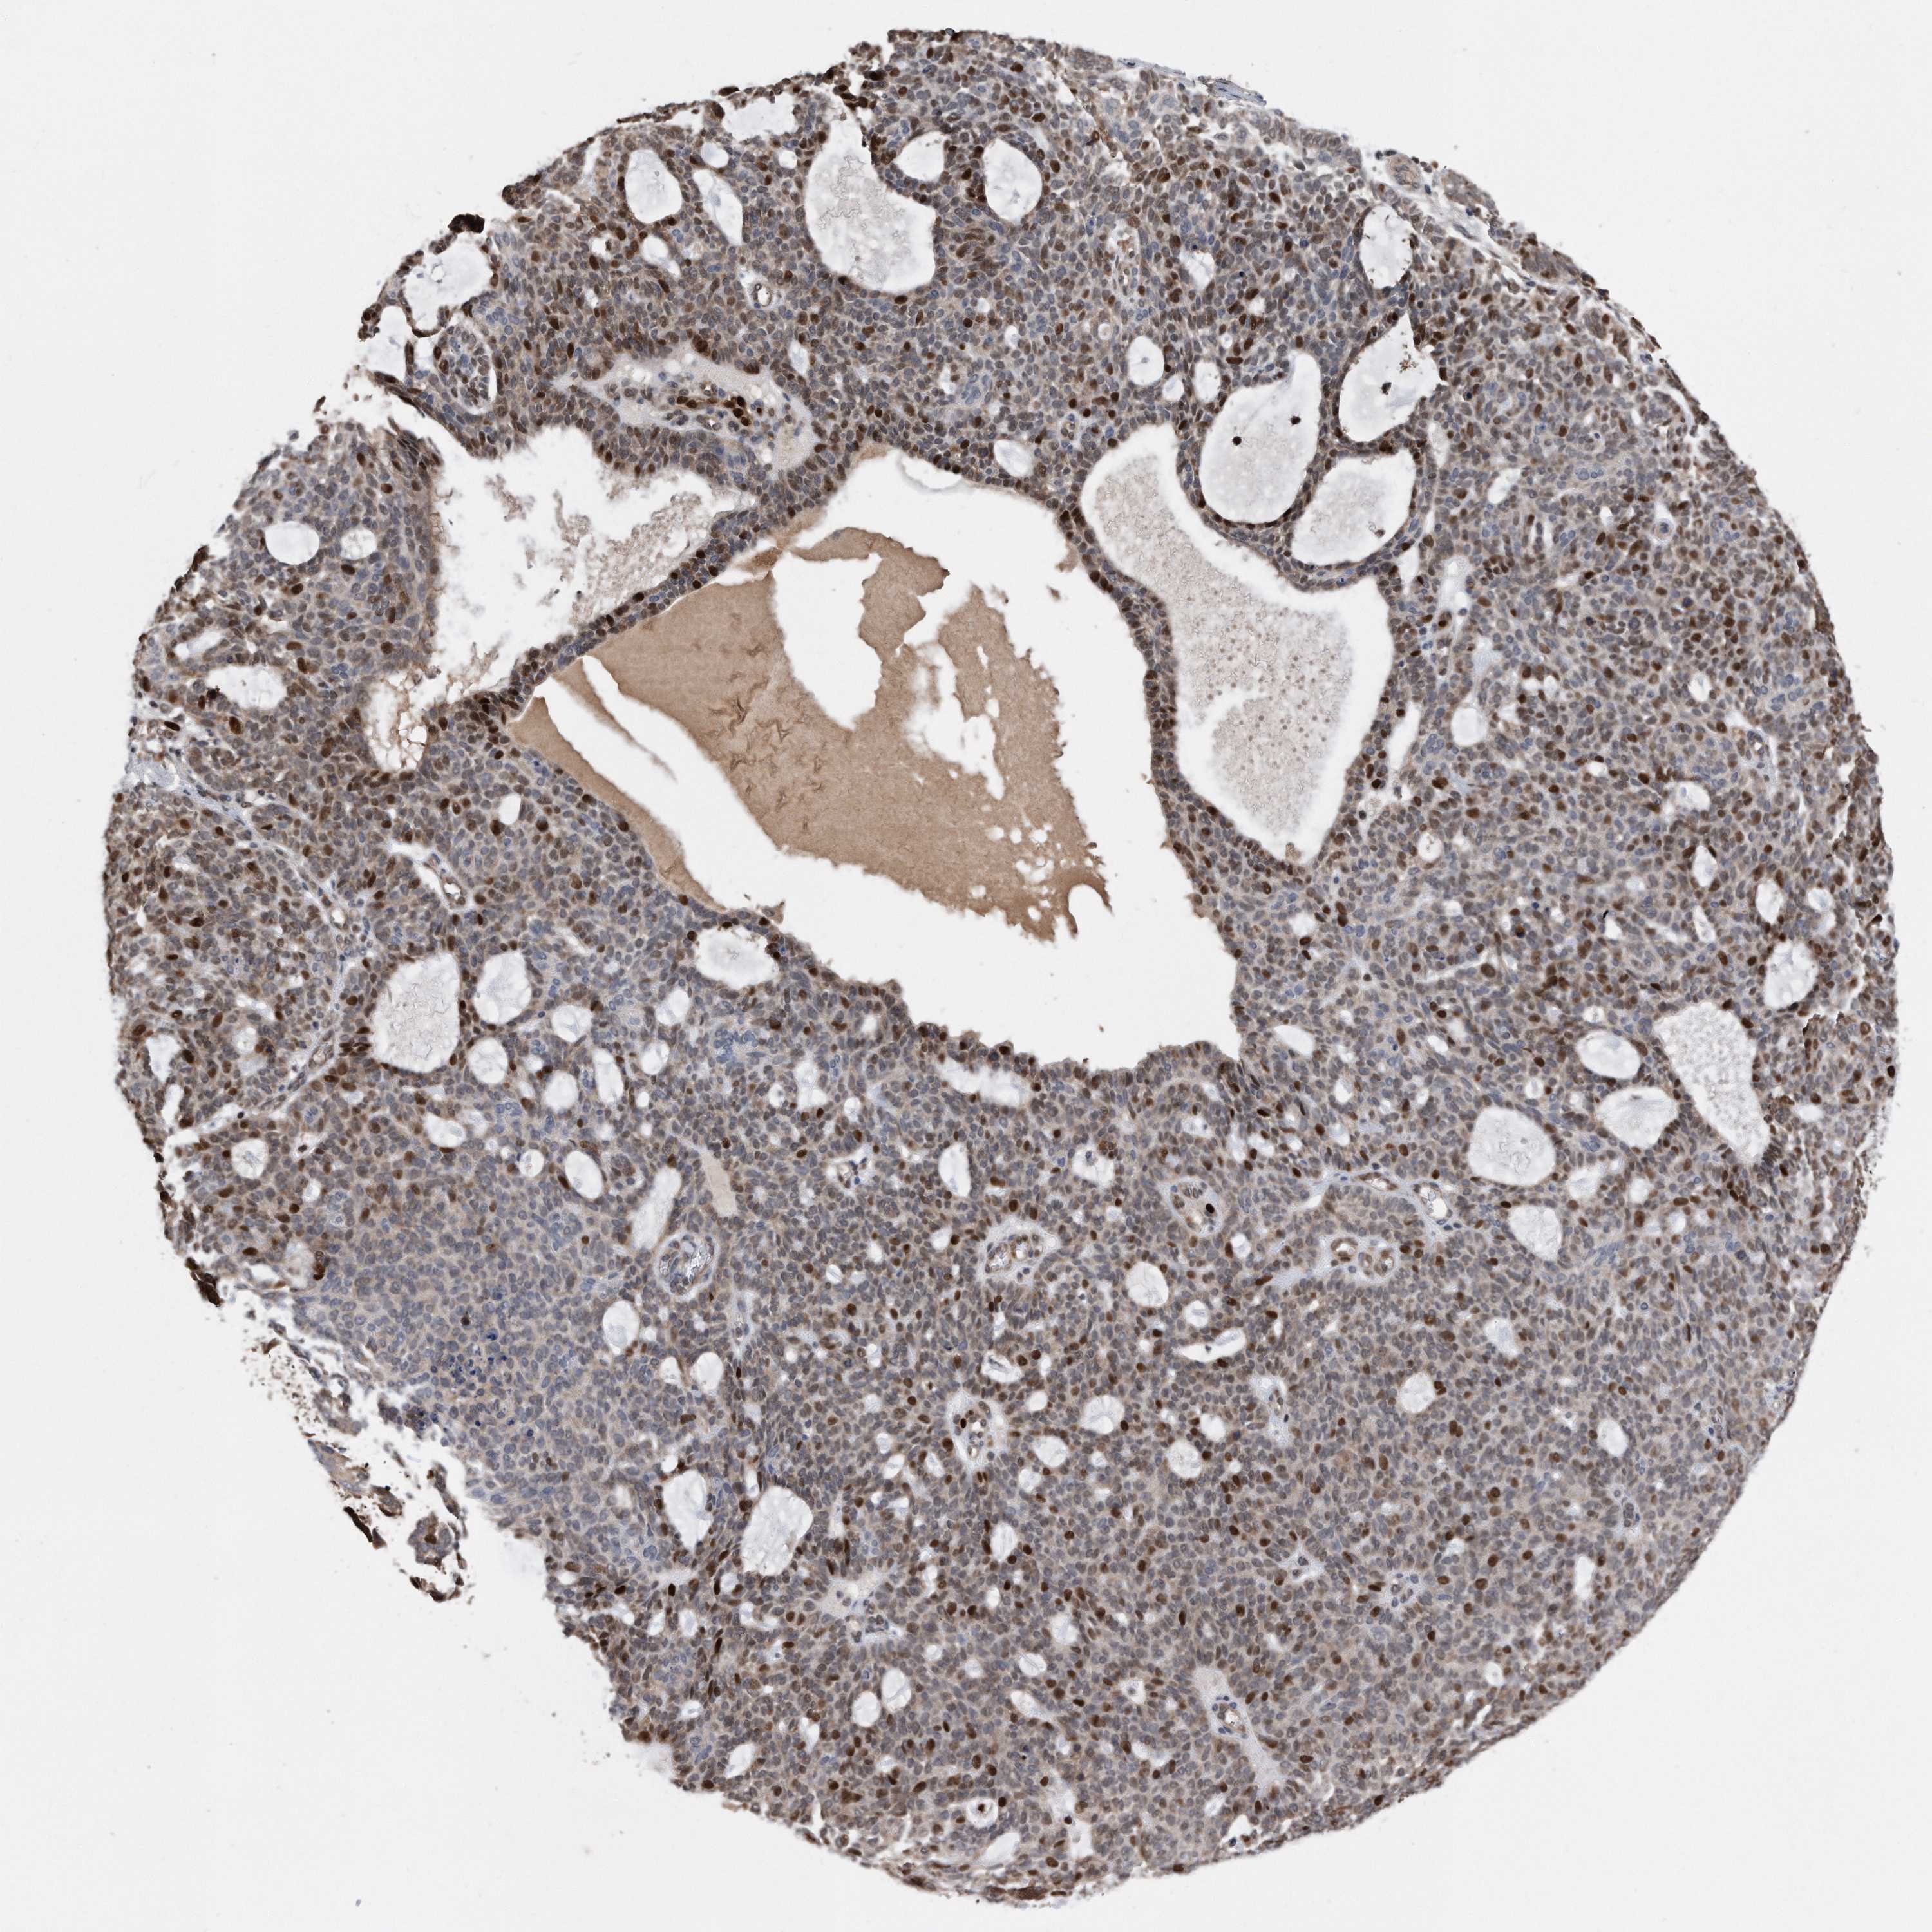

SKIN CANCER - Protein expressioni

A mouse-over function shows sample information and annotation data. Click on an image to view it in a full screen mode. Samples can be filtered based on level of antibody staining by selecting one or several of the following categories: high, medium, low and not detected. The assay and annotation is described here.

Each image is clickable and will lead to virtual microscopy that enables deeper exploration of all samples and also displays staining intensity scores, fraction scores and subcellular localization as well as patient and tissue information for each sample.

HPA030521

HPA030522

HPA030523

CAB000148

CAB080240

CAB080241

CAB080242

Staining

High

Medium

Low

Not detected

Intensity

Strong

Moderate

Weak

Negative

Quantity

>75%

75%-25%

<25%

None

Location

Nuclear

Cytoplasmic/membranous

Cytoplasmic/membranous,nuclear

Basal cell carcinoma

Squamous cell carcinoma, NOS

Squamous cell carcinoma, metastatic, NOS